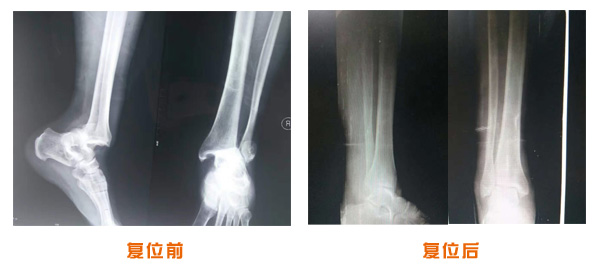

踝關節脫位骨折治療前后對比